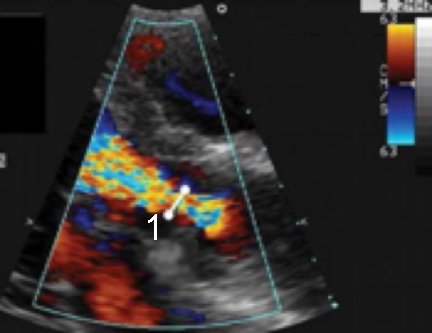

Cardiac 2 Valves Vena Contracta 1 Image Vena Contracta through the aortic valve in a zoomed in image from a Parasternal Long Axis (PLAX) view